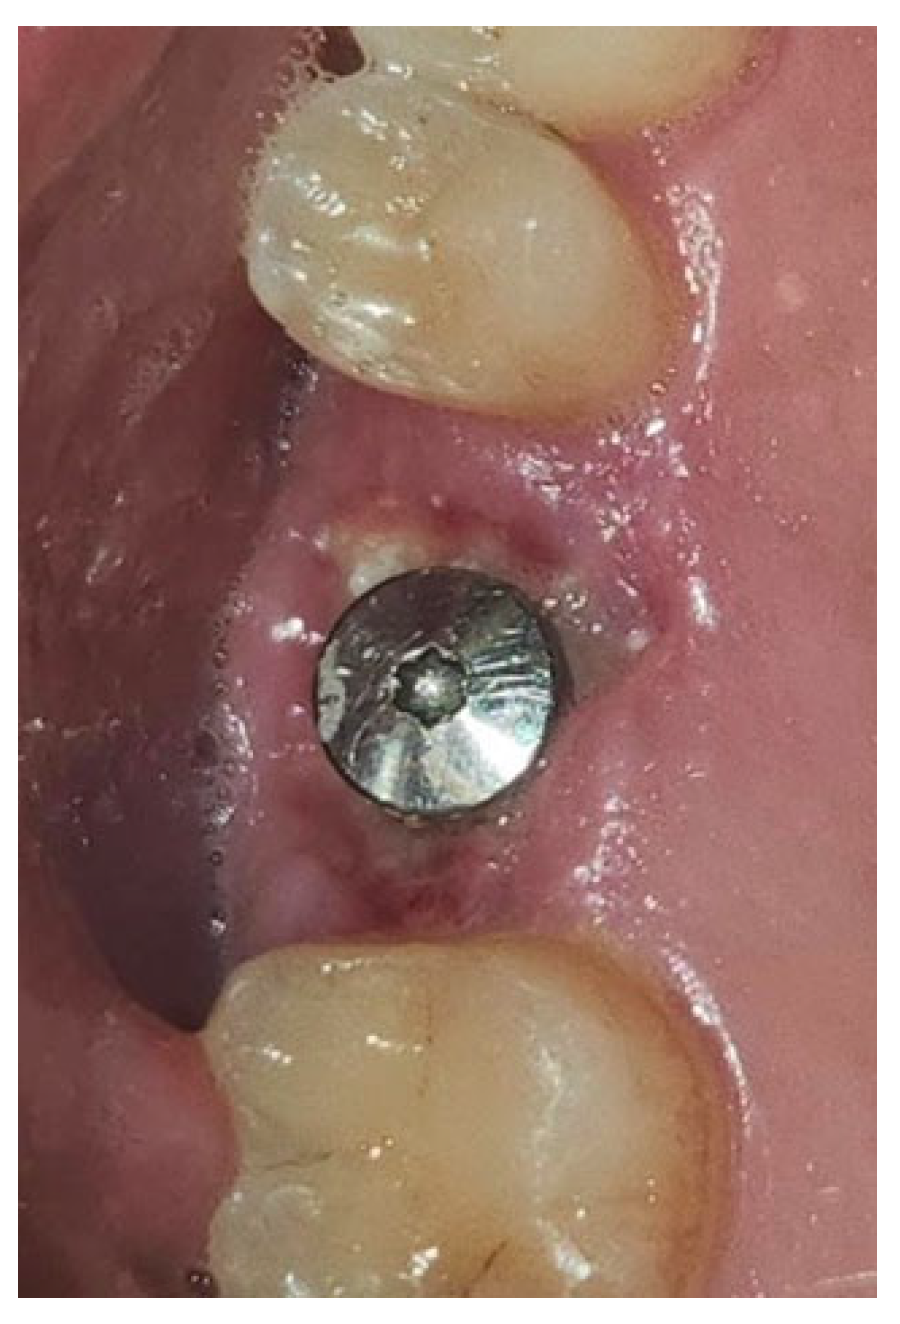

In a 49-year-old patient with ischemic heart disease, Glubran II was used as a stabilizing material for natural bone graft granules at a site rehabilitated with implant-prosthetic treatment, with the aim of achieving volumetric enhancement of the buccal bone. Following specific guidelines for surgical treatment of ischemic heart disease (4), implant therapy was carried out (Figure 8). Natural bone graft material (Bio-Oss®—Geistlich, Baden-Baden, Germany) was applied and stabilized with Glubran II. The application was made using an endodontic needle, depositing single droplets of the glue to cover the entire graft material before placing the prepared flap on top (Figure 9). This technique achieved stable graft fixation at the recipient site, demonstrating the efficacy of Glubran II for internal use (Figure 10).

Figure 8. Implant-prosthetic rehabilitation at site 36; buccal bone level prior to regenerative techniques.

Materials 18 02642 g008